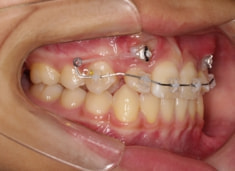

治療開始時

FX(フェイシャルアキシス)は85度なので東洋人の平均値に近く、下顎が前方に過剰成長するリスクは強くはありません。

しかしやはり上顎は劣成長で、下顎が優位な状態ではあります。

上下顎のギャップはありますが、顔面自体の幅径は良好な値を示していますので、スペース不足は拡大することによって解決できポテンシャルはあると考えられます。

左右の非対称もさほど強くありません。